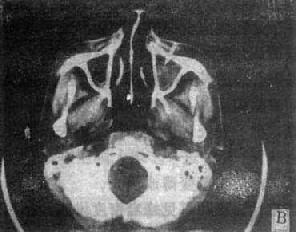

鼻腔和鼻窦内含气体,CT上为低密度区;窦壁、鼻甲和鼻中隔骨质为高密度区,其对比鲜明。

图5-2-5 鼻窦、鼻咽和喉部CT扫描

右上颌窦癌,肿块突入鼻腔和鼻咽部(↓)双上颌窦炎,右侧明显并积液(↑)鼻咽癌,右侧咽壁变直,咽鼓管开口和侧隐窝消失(↑)鼻咽癌,左侧咽壁肿块向咽腔内突起,咽旁间隙侵犯,双上颌窦受累右侧声门癌,右声带增厚并有结节状突起(↑),声门裂变形声门下癌,气管左侧软组织肿块,气道受压变窄

(一)鼻窦肿< 良性病变常见为粘液囊肿和息肉,肿块较小者呈窦腔内密度均匀结节影,边缘光滑锐利,骨壁无破坏;较大者占据整个窦腔,并压迫窦壁使之膨隆扩大,窦壁变薄。一般囊肿的CT值较低。息肉为实性肿块密度较高。恶性肿瘤以鼻窦癌和转移瘤为主。其肿块轮廓多不规则,常伴有窦壁骨质破坏;并伸向鼻咽、鼻腔和眼眶,于该区出现软组织肿块,引起周围脂肪层消失,从而为根治手术或放射野的确定提供可靠的依据(图5-2-5)。